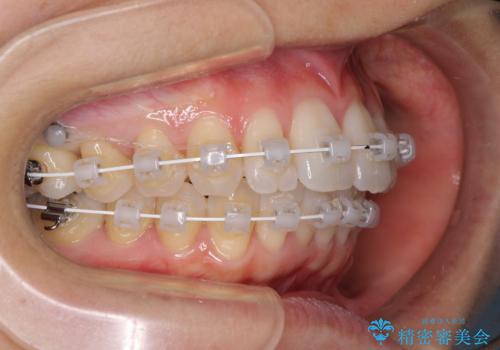

- 矯正装置

- 審美装置

上顎前歯の叢生が解消されると出っ歯になることが分かっていたので、両側奥歯付近にアンカースクリューを入れ、出っ歯を改善するためのゴムかけを行いました。